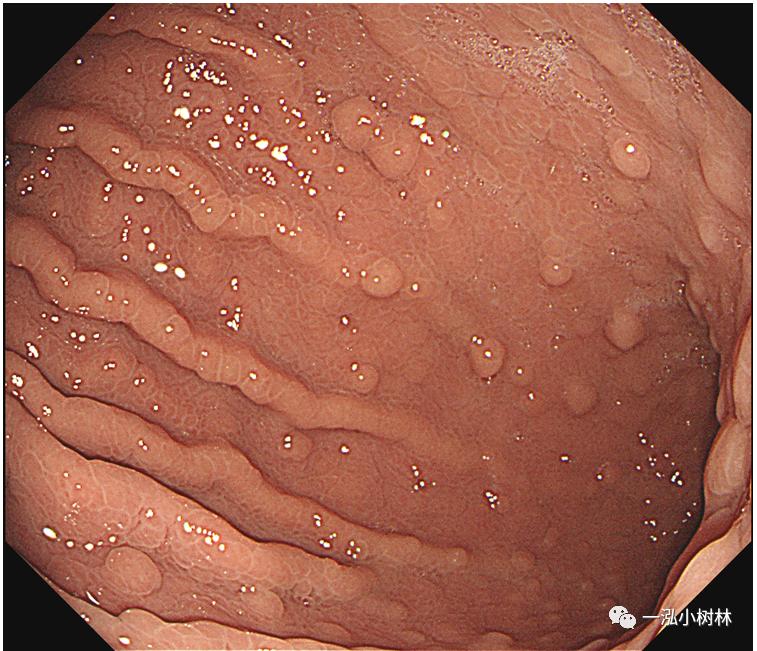

F 23,上腹部不适1年。

白光内镜:胃窦多发息肉

白光内镜:胃体多发息肉